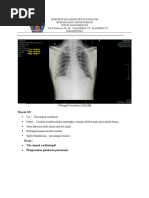

Hasil pemeriksaan Thorax PA:

- Posisi simetris, kondisi film cukup, inspirasi cukup

- Perselubungan inhomogen lapangan tengah paru kanan

- Tidak tampak pemadatan kedua hilus

- Cor : bentuk dan ukuran normal

- Kedua Sinus dan diafragma baik

- Tulang-tulang intak

Kesan : Pneumonia Dextra